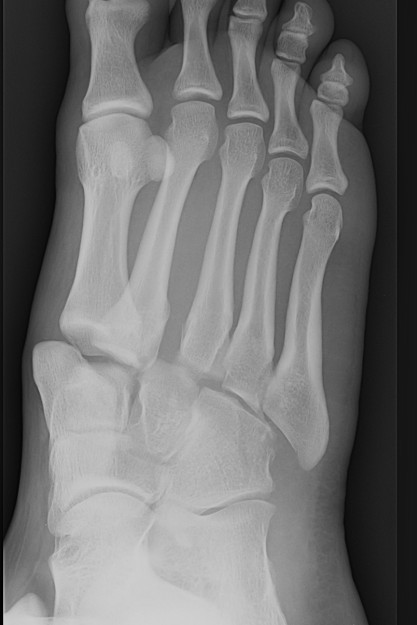

Classification

| Isolated | Homolateral | Divergent |

|---|---|---|

| Only 1st MT injured / displaced | All 5 metatarsals displaced in same direction |

1st metatarsal displaces medially Other 4 metatarsals displace laterally |

| Most common | Least common | |